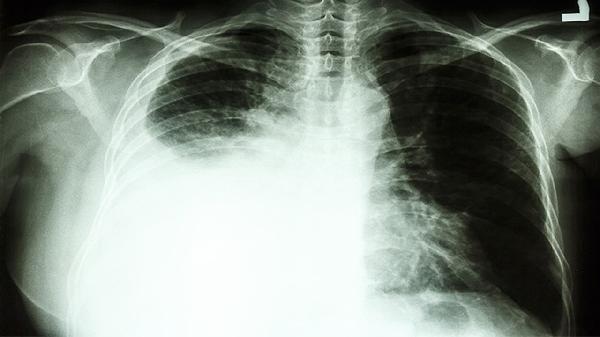

CT照出肺结节,是不是得了肺癌?医生提醒:4类肺结节建议切除

二、这4类结节需要特别关注

2、边缘毛糙的结节

良性结节通常边界光滑,而恶性结节边缘常呈毛刺状或分叶状,就像照片里模糊的轮廓。

3、密度不均匀的结节

CT值超过-600HU的实性成分,或者混合磨玻璃结节中实性占比增大,都需要进一步评估。